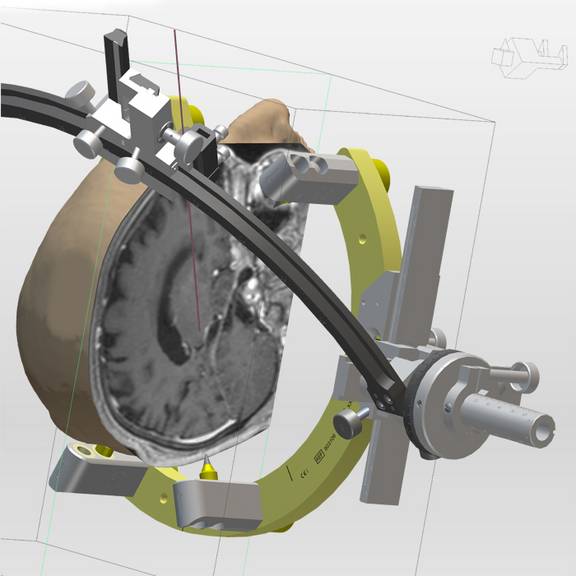

Die Möglichkeit einer schnellen Generierung von 3D Ansichten des Patientenschädels hilft bei der Verifikation der Zielpunktplanung im Zuge der THS. Durch Projektion des verwendeten Stereotaxie-Systems bekommt der Anwender eine realistische Darstellung über Anordnung und Auswirkung der Trajektorie-Planung auf den Systemaufbau.

Das Generieren von Volumen gestattet die Visualisierung von Strukturen, deren Bedeutung für die Zielpunktverifikation bei der THS groß ist. Ob nun Bild für Bild die gewünschte Struktur markiert oder per Softwarefunktion anhand von Schwellwerten automatisch erkannt wird, schlussendlich kann jedes Volumina als Objekt in der 3D-Visualisierung dargestellt werden.

Das inomed Planungssystem iPS unterstützt neben den Stereotaxie-Systemen von inomed auch andere Stereotaxie-Systeme für Eingriffe wie die THS. Nach der Planung werden die ermittelten Daten problemlos auf das jeweilige Stereotaxie-System übertragen.

- 3D-Simulation auf Basis von Patientendaten

- Visualisierung von Trajekten anhand BenGun-Anordnung